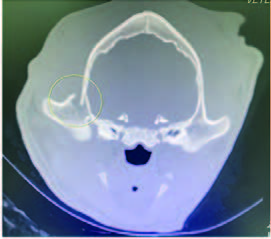

CT scan of skull is preferred for evaluate bone fractures and identify areas of acute hemorrhage or edema. CT scan showed multiple sites of skull fractures, right maxilla, both frontal, right zygomatic, right caudal mandible, right caudal zygomatic, right temporal, left occipital bone (Figure 3) and patchy small area of hyper-attenuation at the cranial of midbrain in pre-contrast study (Figure 4), no detectable mass effect, hypo-attenuated of large edematous parenchyma in the brain, right temporomandibular joint is displacement (Figure 5) and left tympanic bulla shows partial ventral fluid-filled.

CT skull presented to multiple skull fractures, brain edema, midbrain hemorrhage and right TMJ luxation.

Figures 4.1, 4.2

Patchy small area of hyper-attenuation at the cranial of midbrain in pre-contrast study.